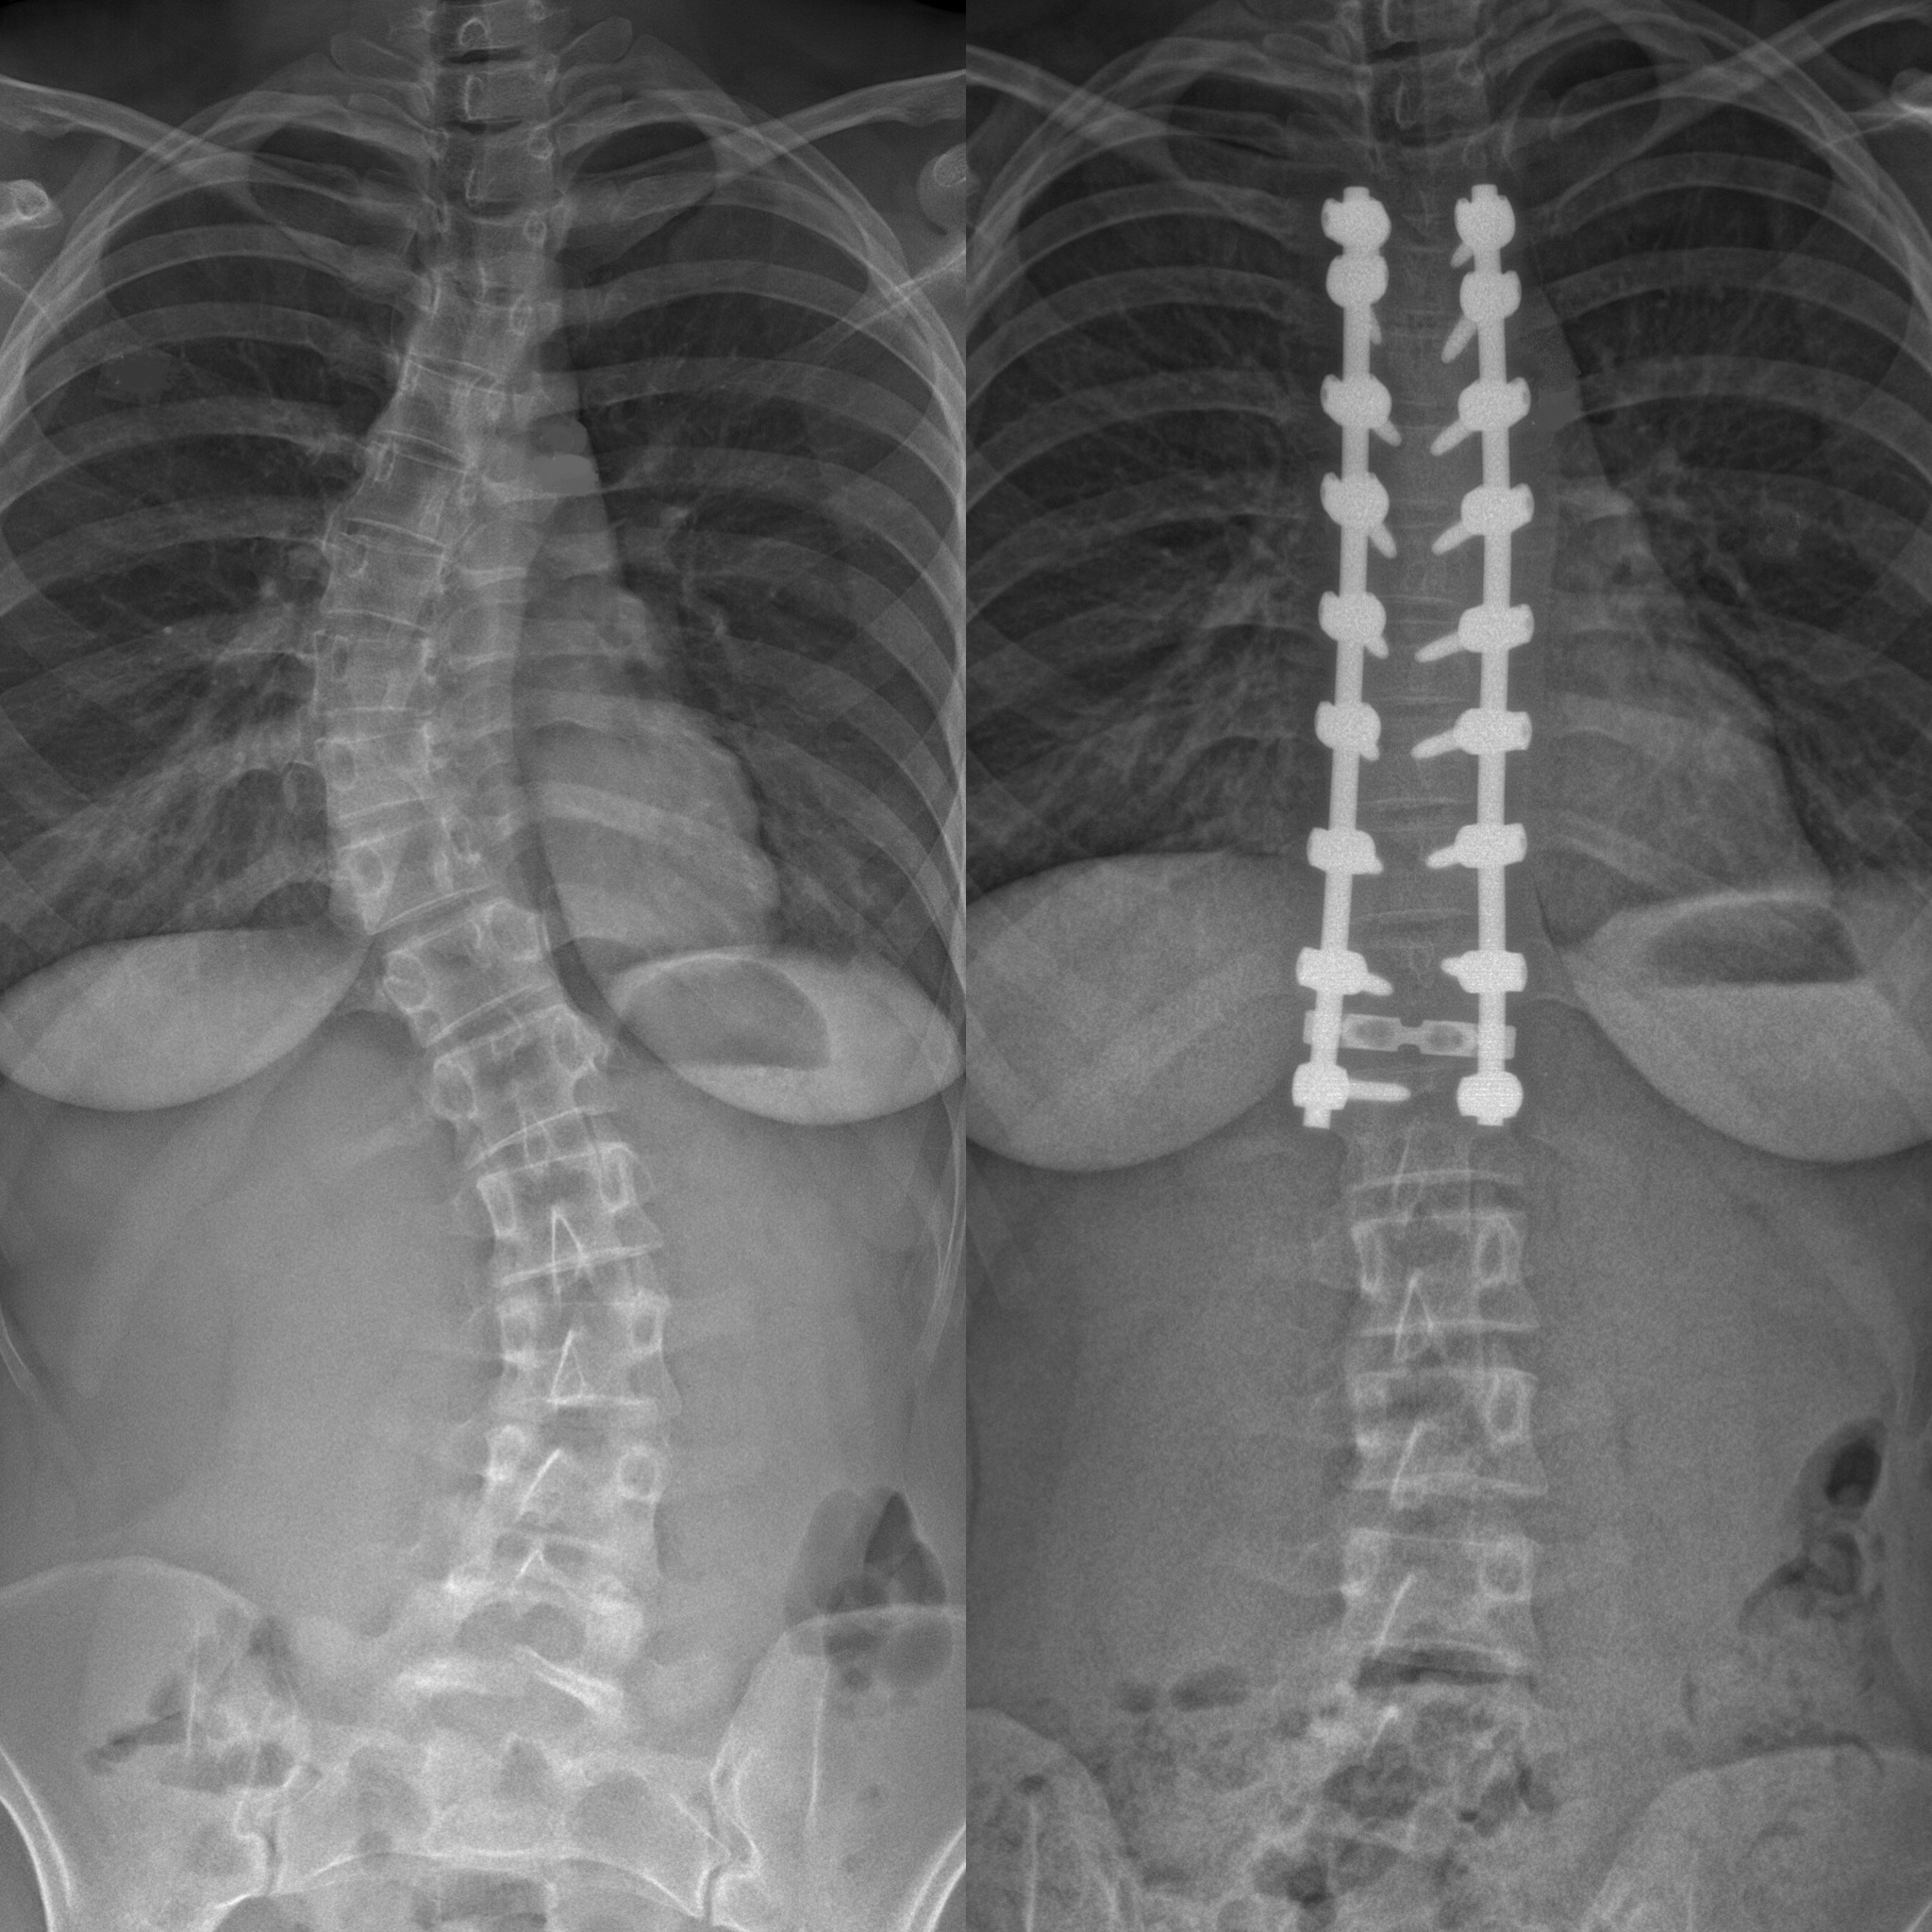

Skolioosissa on kysymys selän vinoutumisesta sivusuunnassa yli 10 astetta mitattuna röntgenkuvasta.

Kouluterveydenhuollossa skolioosin kehittymistä seurataan skoliometrin eli selän vinouden kulmamittausapuvälineen avulla. Yli 6 asteen kierto on merkittävä, ja lapsi tulee lähettää lasten ortopedin arvioon.